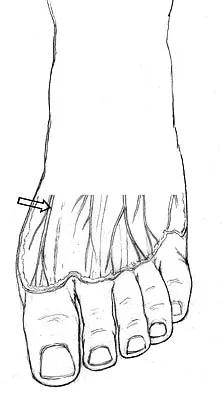

Which of the following structures is most vulnerable during a medial sesamoidectomy of the hallux?

Explanation